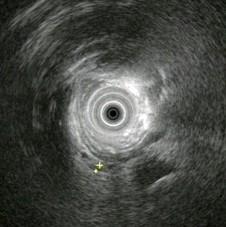

问题 男,42岁,右上腹绞痛反复发作二年,此次发病三天,发冷,发热(38.9℃),,查:巩膜明显黄染,超声内镜如图中病变可能的诊断是 ( )

选项 A.正常 B.胰腺囊肿 C.慢性胰腺炎伴胰管结石 D.胰腺囊腺癌 E.胆总管结石伴扩张

答案 E